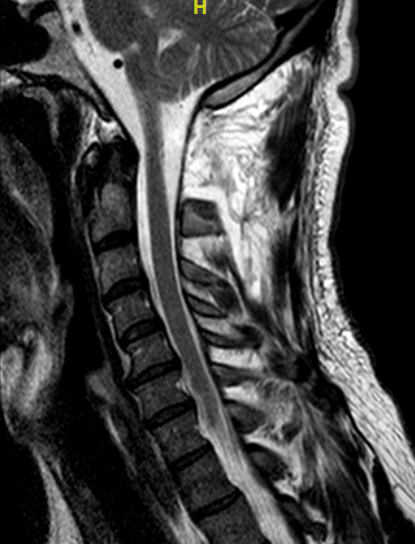

Paciente 34 años que presenta cervicalgia con irradiación a hombro derecho de meses de evolución. En RM cervical se aprecia lesión intradural extramedular informada como schwannoma (menos probable meningioma) a la altura del arco de C1.

Obsérvese la lesión captante, con más tendencia a deformar la médula que a desplazarla (comportamiento que recuerda una lesión intrínseca exofítica)